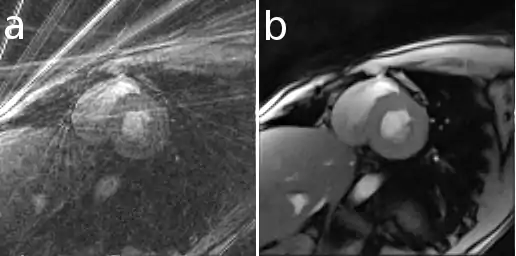

A single frame from a real-time MRI (rt-MRI) movie of a human heart. a) direct reconstruction b) iterative (nonlinear inverse) reconstruction[6]

In Magnetic Resonance Imaging it can be used to reconstruct images from data acquired with multiple receive coils and with sampling patterns different from the conventional Cartesian grid[17] and allows the use of improved regularization techniques (e.g. total variation)[18] or an extended modeling of physical processes[19] to improve the reconstruction. For example, with iterative algorithms it is possible to reconstruct images from data acquired in a very short time as required for real-time MRI (rt-MRI).[6]

Here is an example that illustrates the benefits of iterative image reconstruction for cardiac MRI.[21]